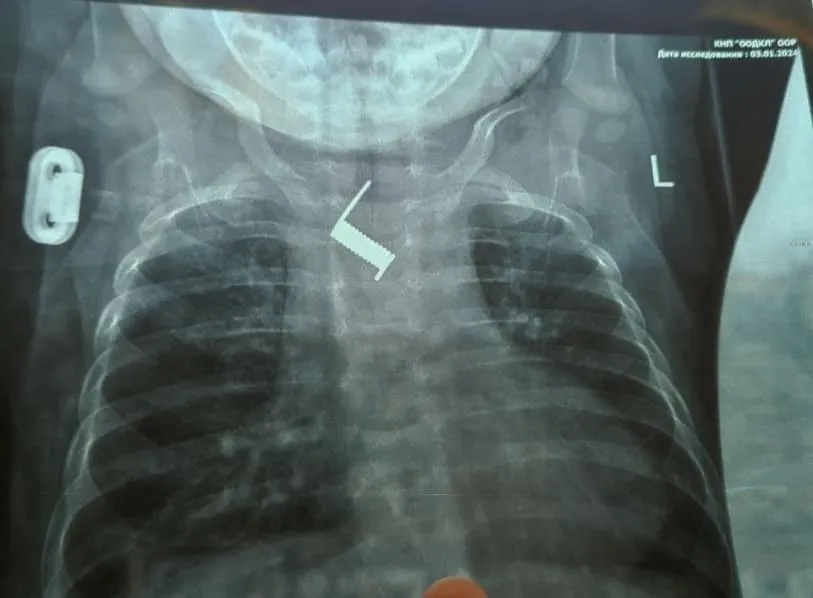

Медики отметили, что через две недели пружина почти вросла в стенку пищевода младенца. После прибытия в стационар больницы была выполнена обзорная рентгенограмма, по результатам которой был обнаружен посторонний предмет в теле ребенка, а именно пружинку от шпильки для волос.

"Находилось постороннее тело на уровне средней трети пищевода, наряду с дугой аорты. Инородное тело было удалено эндоскопически, что избавило ребенка от тяжелого хирургического вмешательства и рисков для жизни", - рассказали медики.